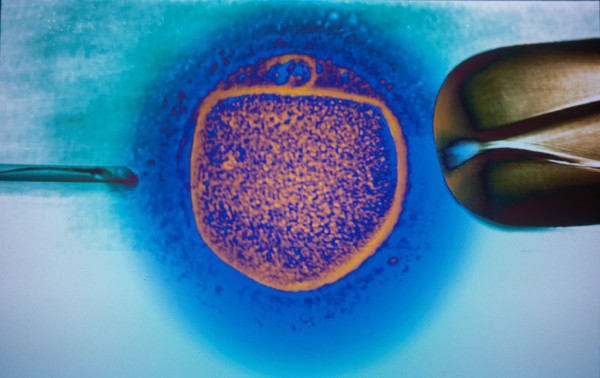

Niedługo rozstrzygnie się, w jaki sposób zostaną uregulowane w naszym kraju procedury medyczne zapłodnienia pozaustrojowego. Finał tej sprawy będzie ważnym probierzem postępów, jakie czyni w Polsce liberalna demokracja.